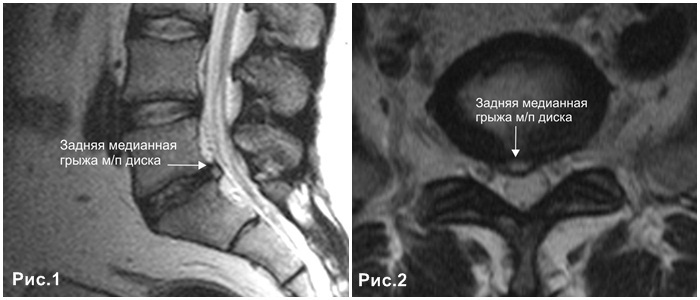

КТ-протрузии дисков: Визуализация и классификация